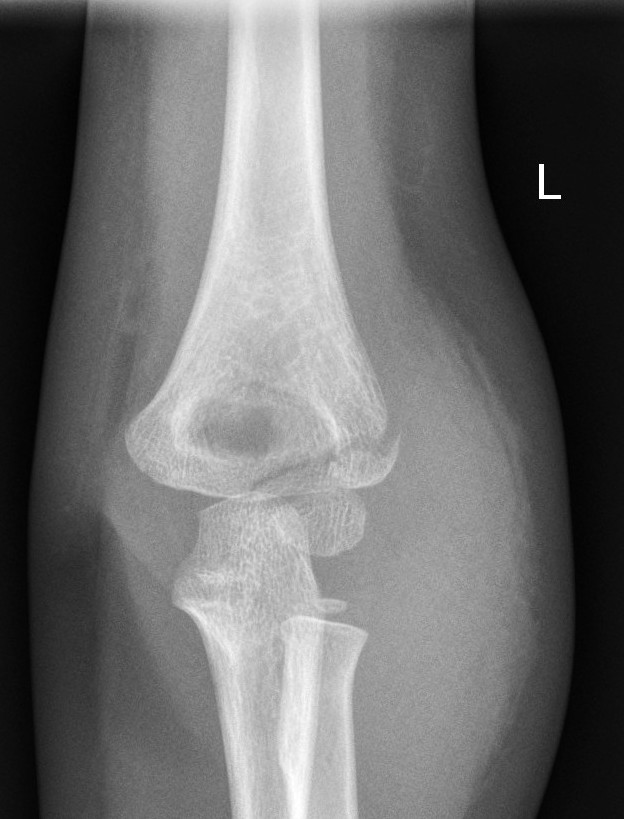

6. Look for obvious fracture lines on the AP view

|

Supracondylar fracture evident on the AP view |